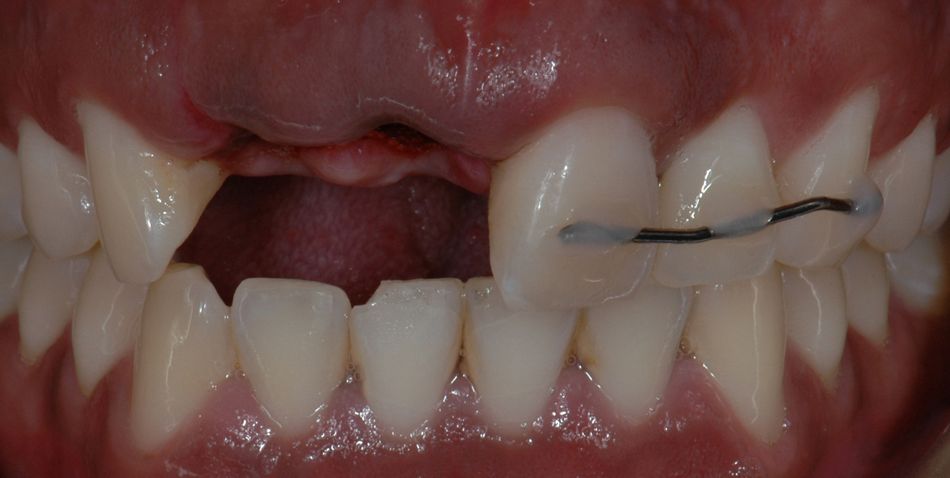

A healthy 27-year-old male suffered the avulsion of both central and lateral upper right incisors, during a street attack. At first, he attended to an emergency clinic in which the remaining teeth were splinted, and no effort was made to replace the avulsed teeth. (Fig. 1)

The clinical and radiological exams showed no signs of bone or adjacent teeth fracture. Nevertheless, we decided to take a CBCT for better planning of the case. In fact, bone plates were intact. Still, buccal bone plate showed thin and fragile. In cases like this, apical anchorage is the only way to increase primary stability. (Figs. 2-3) First approach was a removable partial denture made up with ovate pontics, as to preserve soft tissue shape. To increase primary stability, Straumann® BLX implant was the best option. With its unique functional design, it provides simplicity and immediacy. Progressive thread design compacts bone, increases its density and thus, increases strength. It cuts, collects, and condenses native bone, achieving almost perfect BIC (bone-to-implant contact).